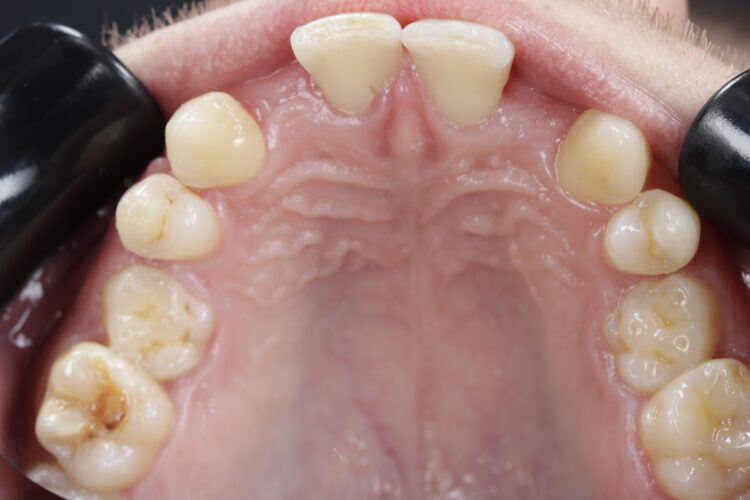

Before placing the final crowns, the patient opted for a teeth whitening procedure to ensure the new crowns matched a brighter shade. The whitening was an at home procedure and was reviewed in November 2023 before a final shade match was taken.

Final crowns placement (November 2023)

The final implant crowns were fitted in November 2023. There was a slight delay due to the patient postponing some appointments and undergoing whitening treatment.

The patient achieved an aesthetically pleasing and functional result and he expressed satisfaction with the outcome.